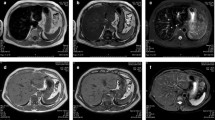

Two of the 5 patients with genetically confirmed HFE-HC who presented in heart failure were rescanned after venesection (Figure 4). Both repeat scans showed a considerable improvement in the LV EF and myocardial T2*.

Examples of CMR scans from newly presenting patients with C282Y homozygous hemochromatosis and heart failure. a) 54 year-old male with presenting myocardial T2* of 5.4 ms and LVEF of 36%. When rescanned 31 months later after venesection, the cardiac T2* had improved to 15.7 ms, and the LVEF to 65%. b) 59 year-old female with presenting cardiac T2* of 7.4 ms and LVEF of 35%. Rescanning 19 months later after venesection showed improvement in T2* to 23.6 ms and LVEF to 61%. In both cases, venesection resulted in considerable improvement in iron loading and cardiac function. Top row: horizontal long axis, middle row: mid-ventricular short axis, bottom row: vertical long axis.